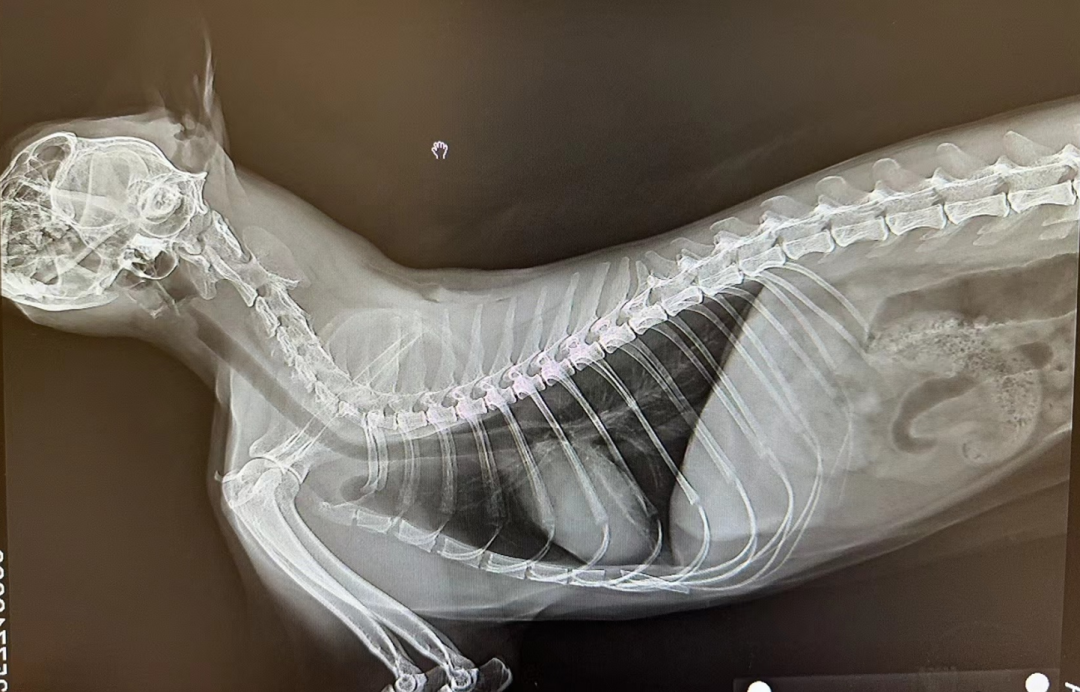

在接到求助后,我们的医生立即准备了专业的圆头镊子等工具,为猫咪进行了详细的检查。经过拍片等仔细检查工作,医生发现猫咪的喉咙确实卡着一根细小的鱼刺。在安抚好猫咪后,医生迅速而准确地使用圆头镊子将鱼刺取出。整个过程中,小猫表现得非常勇敢,配合度极高,让在场的所有人都为之感动。